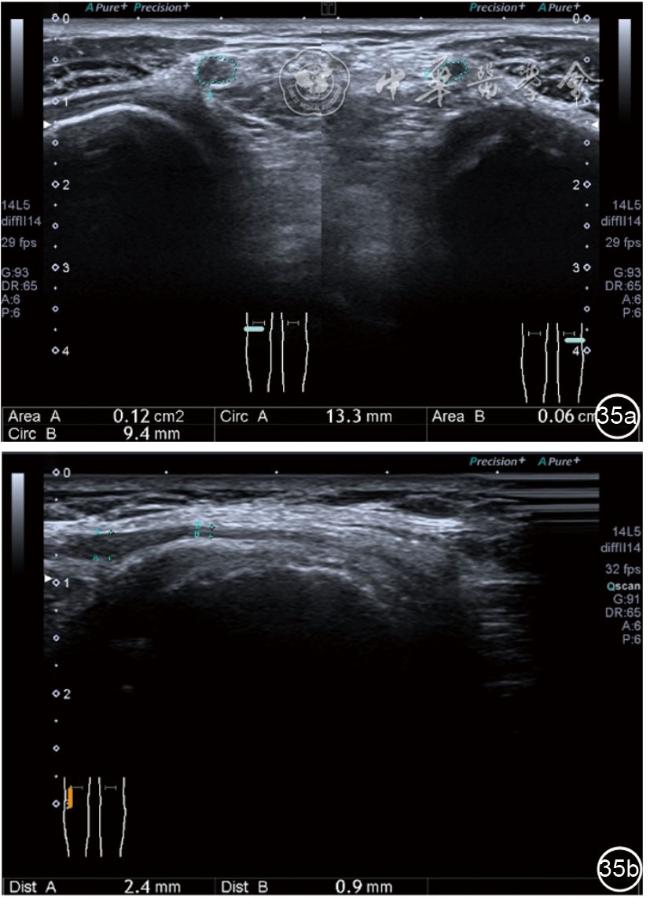

患者采取侧卧位,患肢在上,屈膝20°。应用10~18 MHz高频线阵探头,扫查深度1~3 mm。长轴和短轴结合双侧对比扫查。超声影像学所见:短轴可见卡压腓总神经近端增粗,面积增大;长轴可见腓总神经卡压处变细,其近侧肿胀、回声减低,而在卡压远侧则表现正常(图35);一些受压严重者可以出现神经周围积液,卡压神经部位的筋膜增厚(图36);受压神经内血流增加对临床诊断意义更大(图37);探头在病变神经处加压常可引起神经刺激症状。腓总神经支配的肌肉有失神经支配改变,表现为肌肉回声增高和肌肉萎缩(图38)。

图35 超声短轴可见卡压腓总神经近端增粗,面积增大;长轴可见腓总神经卡压处变细,其近侧肿胀、回声减低